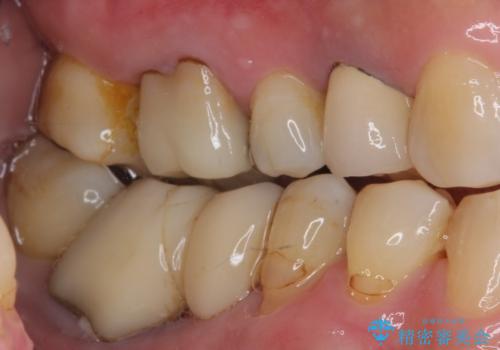

- 60歳を越え、黄ばんだ前歯をセラミッククラウンできれいな口元にしたいとのことで来院された患者様です。

診察したところ、前歯は反対咬合であり、その影響で抜歯が必要な奥歯があることが分かりました。

抜歯が必要な奥歯は、インプラント並びにブリッジにより補綴を行い、上下前歯は反対咬合を改善させるように補綴治療を行うこととしました。

健全な歯を削ってセラミッククラウンに置き換えることは、本来避けるべき治療と考えますが、今回は①患者様が60歳を越えていること、②要改善の咬合により抜歯が必要な奥歯があること、③反対咬合の前歯改善の手段としてセラミック治療が選択肢にあることなどから、全顎的なセラミック治療を行うこととしました。